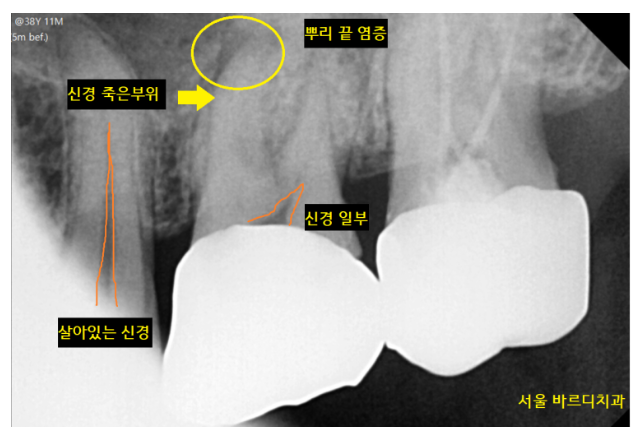

불편을 호소하시는

왼쪽 위에 치아를 검사해보았습니다.

이런 이런..

신경이 죽었네요.

신경이 살아있으면

검정색 선이 보이는데요.

환자분은 신경이 안보였습니다.

신경이 이미 괴사

죽어버려서 검정색 선이 없어졌네요~~

비가역적 치수염으로 진단되었습니다.

신경이 죽은 치아 뿌리 끝에 염증이 보이고

상악동까지 염증이 번져서 눈 두덩이가 아픈거라

치료가 필요했습니다.

환자분은 만성 비가역적 치수염

염증이 오래된 상황이었습니다.